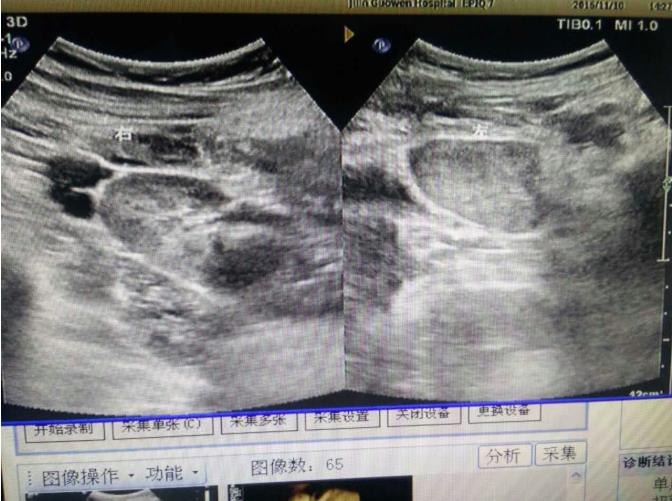

為該患常規(guī)檢查臍帶入口時(shí)發(fā)現(xiàn)臍帶入口位于胎盤下緣邊緣,胎兒超聲檢查無陽性發(fā)現(xiàn)。常規(guī)掃查右卵巢時(shí),發(fā)現(xiàn)右卵巢旁可見腎臟回聲(正常情況下,右卵巢旁是不會(huì)掃查到腎臟回聲的),大小、形態(tài)如常,CDFI:腎內(nèi)血流灌注尚可,故囑患者左側(cè)臥位,顯示孕婦右腎位置、大小及形態(tài)正常,囑孕婦右側(cè)臥位,發(fā)現(xiàn)脾臟下方無腎臟回聲,故考慮該患左腎游走腎。該患于2016年12月2日復(fù)查,結(jié)果如前。

正常腎位置是腎門相當(dāng)于第一、第二腰椎橫突,右側(cè)略低于左側(cè),立位時(shí),腎可下降2—5cm,約相當(dāng)于一個(gè)椎體,超過此范圍者,稱為腎下垂,少數(shù)患者腎被腹膜包裹而腎蒂松弛,能在腹部范圍移動(dòng),有的甚至降到下腹部或骨盆內(nèi),或跨過中線到對(duì)側(cè)腹部,此類腎下垂稱游走腎,一般多見于右側(cè)。